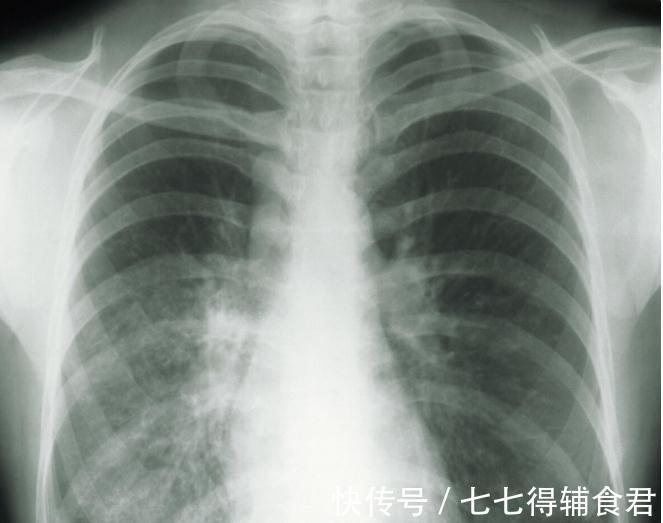

文章插图

咱们就来聊一聊长了肺结节该怎么办

首先肺结节并不等于肺癌。实际上20%的成年人存在肺结节80%的肺结节只是单纯的肺结节一般结节越大危险性越高如果你检查结节直径小于10mm一般情况下定期复查就可以了。如果检查出来磨玻璃结节这种容易恶变一定要多加重视。一般像长期吸烟、直系亲属有肺结节、肿瘤的、有工业粉尘、石棉及放射性物质接触史、年龄在40岁以上伴随有胸痛、咳嗽、不明原因的痰中带血丝、消瘦、体重下降等情况的肺结节人群一定要比别人更加重视这个问题。